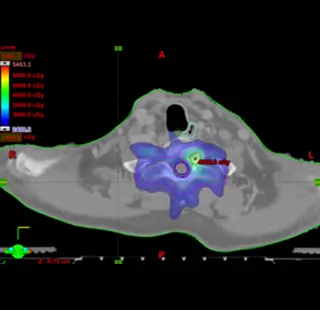

세기조절 방사선치료 (IMRT; Intensity Modulated Radiation Therapy)

치료목적에 최적화된 방사선분포를 치료부위에 전달하면서 주위 정상 조직에는 방사선 조사를 최소화시키는 목표를 컴퓨터를 이용한 역방향치료계획을 사용하여 구현하는 최첨단 방사선치료입니다.